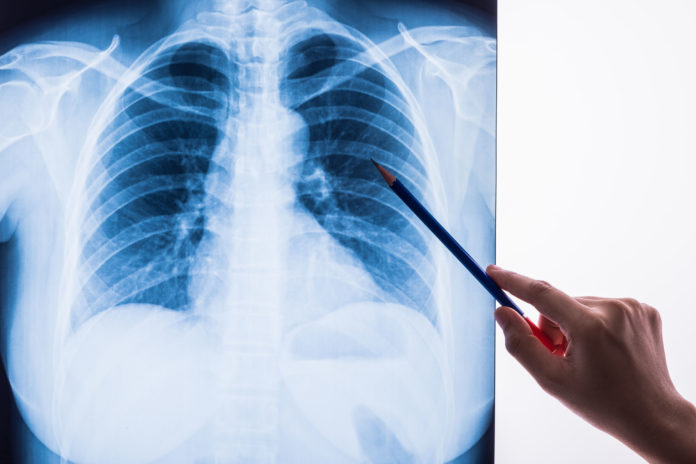

Epidémie de coronavirus oblige, les malades atteints de bronchopneumopathie chronique obstructive (Bpco), sont en première ligne. Pourtant aucun message d’information ne leurs est destiné. Dans une lettre adressée au ministre de la Santé, ils montent au créneau pour dénoncer le manque de visibilité et de prise en charge de cette maladie, qui touche 4 millions de personnes en France.

Le Covid-19 fait en priorité des dégâts chez les personnes atteintes de maladies pulmonaires et notamment celles qui souffrent de Bpco. Problème ? « La réponse médicale est quasi-inexistante, si ce n’est en réanimation pour les quelques-uns qui seront assez résistants physiquement pour espérer un rétablissement, ce qui n’est pas le cas de 90% des malades au moins », s’insurge l’association France-Bpco dans une lettre adressée au ministre de la Santé, Olivier Véran.

La Bpco, une maladie peu connue

L’association reproche aux autorités sanitaires, l’absence de messages d’alerte à destination de ces malades. Pourtant, la Bpco, pathologie grave et invalidante du système pulmonaire frappe à tout âge.

Elle touche 4 millions de personnes en France, dont 700 000 dans une forme grave. 80% ont moins de 64 ans, et les plus jeunes ont moins de 20 ans. Sa cause principale est le tabac. Deux tiers des malades ignorent qu’ils en sont atteints.

Pour ces patients, l’épidémie de covid-19 est bien plus qu’une maladie, c’est « une menace de mort », d’après l’association France Bpco.